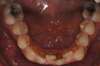

Encombrements traités par gouttières

G-Intermédiaire 3